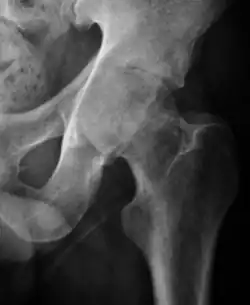

Plain radiography allows us to categorize the hip as normal or dysplastic or with impingement signs (pincer, cam, or a combination of both). Besides these, pathologic processes like osteoarthritis, inflammatory diseases, infection, or tumors can also be identified (Figure 1).[1]

Figure 1.

-

Radiography in normal hip -

X-ray in pincer impingement type of hip dysplasia -

X-ray of cam -

Hip in osteoarthritis -

Septic arthritis

Projectional radiography ("X-ray") is the first imaging technique of choice in hip pain, not only in older people with suspected osteoarthritis but also in young people without any such suspicion. In this case plain radiography allows categorization as normal hip or dysplastic hip, or with impingement signs, pincer, cam, or a combination of both.[1]

Projectional radiography ("X-ray") is currently useful not only in older people in whom osteoarthritis of the hip is suspected but also in younger people without osteoarthritis, who are being evaluated for femoroacetabular impingement (FAI) or hip dysplasia.[1]